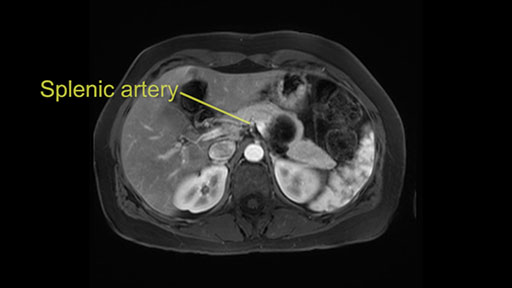

The second slowing down moment or consideration I give to a distal pancreatectomy is the anatomy of the portal vein and the splenic artery. And so I look here and the anatomy is pretty straightforward. The splenic vein comes off normally and runs behind the pancreas and I can see the artery superior to that, again coming off in a normal manner from the celiac axis. So those two things, the portal vein and the splenic artery will be taken normally in this procedure.

I think the splenic vein, once I have slowly teased it off from the cyst and from the retropancreatic parenchyma, I would put a vessel loop around it to serve as a traction. So once you have the vessel loop or probably umbilical tape, to retract or pull the pancreatic parenchyma while we slowly tease it off and try to move superiorly to be able to expose the splenic artery. That is again another slow-down moment because sometimes we think that it is the splenic artery at the superior edge of the pancreas, but it could also be the hepatic artery as it branches from the celiac artery.